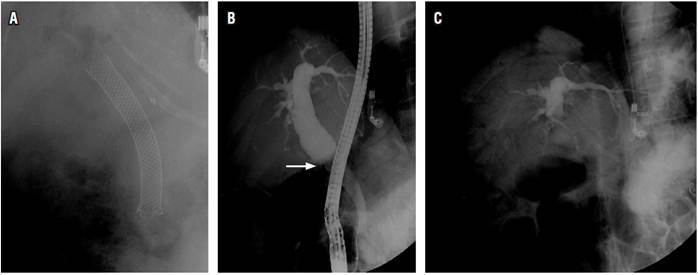

Mujer de 55 años, con trasplante hepático en 2007 por síndrome de Budd-Chiari, que desarrolló estenosis anastomótica biliar. Se manejó mediante CPRE durante 1 año (dilataciones neumáticas, inserción de prótesis biliares plásticas). Por recurrencia de la estenosis biliar se insertó un stent metálico autoexpandible (SMAE) completamente recubierto (80 mm por 10 mm). A los 4 meses consultó por dolor abdominal, se realizó una ecografía abdominal que mostró dilatación del colédoco (20 mm) con cálculos en su interior. Los paraclínicos mostraron elevación de la fosfatasa alcalina (3x) con bilirrubinas y transaminasas normales (fosfatasa alcalina: 290 UI/L, valor normal: 32-91; aspartato-aminotransferasa [AST]: 25 U/L, valor normal: 15-51; alanina- aminotransferasa [ALT]: 31 U/L, valor normal: 17-63; bilirrubina total: 0,9 mg/dL, valor normal: 0,3-1,2; bilirrubina directa: 0,2 mg/dL, valor normal: 0,1-0,5). Se realizó una CPRE bajo anestesia general. En la radiografía preliminar se apreció el stent biliar metálico y neumobilia proximal (Figura 1A). En la duodenoscopia se observó que el SMAE ha migrado proximalmente; se introdujo un balón extractor en su interior, se insufló, se traccionó, se expuso parcialmente su extremo distal en luz duodenal y se logró extraer con una pinza de cuerpo extraño. Al examinarlo, el SMAE tenía su lumen totalmente obstruido por cálculos y barro biliar.

La colangiografía mostró una vía biliar extrahepática dilatada (colédoco proximal de 18 milímetros de diámetro) y la anastomosis biliar sin estenosis (Figura 1B). Se instrumentó la vía biliar con balón, con extracción de cálculos residuales. En la placa final había importante neumobilia que comprometía además los pequeños conductos biliares proximales intrahepáticos (Figura 1C). En el posoperatorio inmediato (paciente aún intubada) se documentó un ritmo de taquicardia ventricular seguido de un trazo de actividad eléctrica sin pulso; presentó desaturación, hipotensión, cianosis y marcada ingurgitación yugular, se iniciaron medidas de reanimación, y el retorno a circulación espontanea se obtuvo después de 2 minutos, con administración concomitante de 1 mg de adrenalina, 300 mg de amiodarona, 60 meq de bicarbonato e infusión de norepinefrina (0,25 µg/k/m). Se accedió a la vía venosa central subclavia derecha.

La extracción de una prótesis obstruida y la instrumentación de la vía biliar con balón, asociado con una comunicación amplia entre la vía biliar y la luz duodenal por la papilotomía previa, produce una presión negativa en el árbol biliar que facilita el paso rápido del aire del duodeno hacia la vía biliar intrahepática, lo cual se demuestra en la placa final de la CPRE (importante neumobilia que compromete los pequeños conductos biliares intrahepáticos en forma generalizada). Este aire en la vía biliar (en abundante cantidad y rápidamente ingresado) puede difundir fácilmente hacia la circulación sistémica (cavidades cardíacas derechas) a través de las venas hepáticas, lo cual pudo constituir otro mecanismo adicional para la embolia aérea 3.